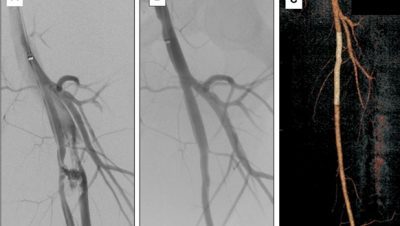

-  خامسا: “الدعامه المغطاه”:

– تستخدم الدعامه المغطاه لعلاج انسداد شريان الحوض لتميزها بالجدار الاملس مما يحسن عمر الدعامه

– تستخدم ايضا لعلاج القرح الشريانيه في الحالات الصعبه اوالتمدد الشرياني او في بعض المضاعفات والحالات المرتجعه

– تستخدم في الطواريء انقاذا للحياه في حالات التسريب الشرياني او النفجار الشرياني التي قد تحدث في مثل حالات الاصابه والحوادث